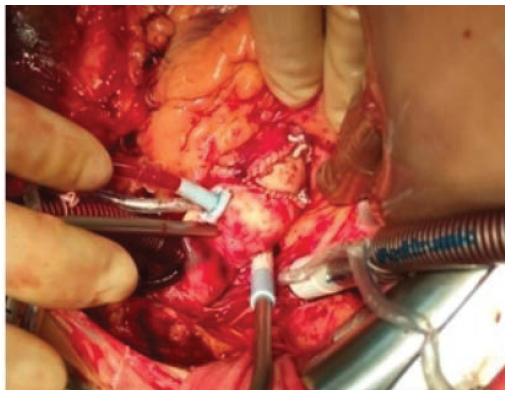

Интраоперационно аортальный клапан трехстворчатый, с выраженным кальцинозом створок. Обращает на себя внимание малый размер корня аорты. Произведено иссечение створок аортального клапана. При измерении диаметра базальное кольцо корня аорты не пропускает измеритель №19. Выполнена анну- лорасширяющая реконструкция корня аорты по методике Nicks: корень рассечен по середине некоронарного синуса до уровня базального кольца, в эту область имплантирована клиновидная заплата из ксеноперикарда (рис. 2). В позицию аортального клапана имплантирован биологический протез №21. Восстановление целостности стенки аорты произведено полипропиленовой нитью 5-0. Следующим этапом выполнены маммарокоронарное шунтирование и резекция ушка левого предсердия. Синусовый ритм восстановлен после разряда дефибриллятором.

Рис. 2. Б. Общий вид корня аорты после расширения.